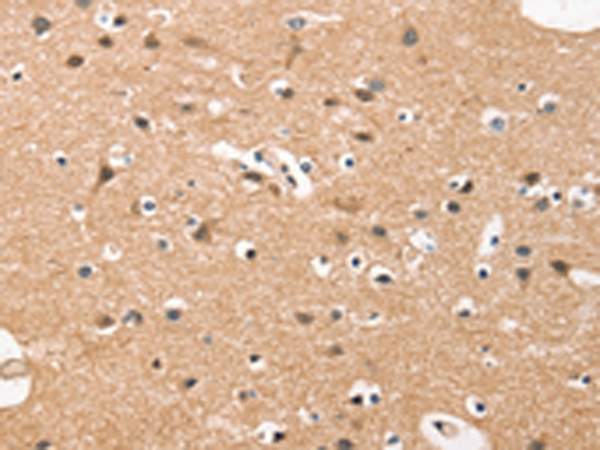

IHC positive control: |

Human brain and human esophagus cancer |

IHC Recommend dilution: |

50-200 |